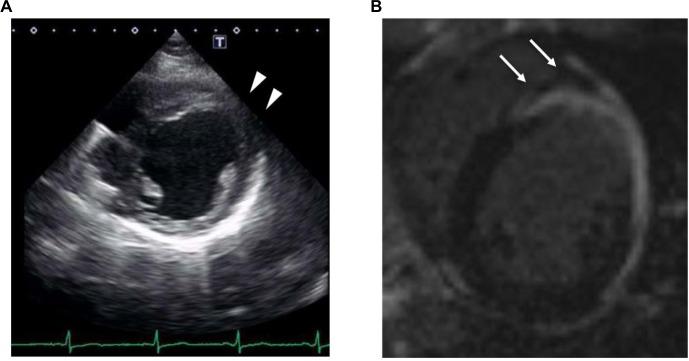

Cardiac magnetic resonance imaging (MRI) is a useful tool for detecting the arrhythmogenic substrate in cardiac sarcoidosis. We herein present a case of bipolar radiofrequency catheter ablation for ventricular tachycardia (VT) complicated with cardiac sarcoidosis, guided by pre-procedural cardiac MRI. Neither echocardiography nor endocardial voltage mapping suggested a septal VT substrate. However, MRI alone detected intramural lesions in the septum. Although application of endocardial energy failed to treat the VT, bipolar ablation targeting the potential substrate identified by MRI successfully eliminated the VT. Even when no abnormalities are depicted on echocardiography and endocardial voltage mapping, intramural scar tissue identified by cardiac MRI could be critical for VT.

摘要

心脏磁共振成像(MRI)是检测心脏结节病中致心律失常基质的有用工具。我们在此介绍一例在术前心脏MRI引导下,对合并心脏结节病的室性心动过速(VT)进行双极射频导管消融的病例。超声心动图和心内膜电压标测均未提示室间隔VT基质。然而,仅MRI检测到室间隔壁内病变。尽管心内膜能量应用未能治疗VT,但针对MRI确定的潜在基质进行双极消融成功消除了VT。即使超声心动图和心内膜电压标测未显示异常,心脏MRI确定的壁内瘢痕组织对VT可能也至关重要。